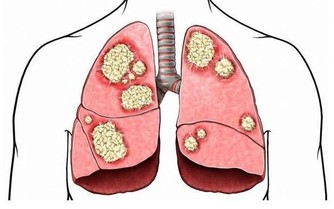

2.細菌性痢疾與腸癌傻傻分不清

腸癌潰破合併感染後會出現與細菌性痢疾相似的膿便血、腹瀉、裡急後重等症狀,所以臨床50%的腸癌都被誤診為細菌性痢疾。通過深一步診斷與乙狀結腸鏡檢查可分辨。

3.潰瘍性結腸炎與腸癌互相混淆

潰瘍性結腸炎其實也是一種重病,暫無特效藥,被譽為“不死癌症”。與腸癌都有便血、腹部不適等相同的症狀,如果兩者不能準確診斷,都會耽擱病情,治療困難重重。同時,潰瘍性結腸炎長期會誘發癌變,讓治療更是難從下手。

5.結腸結核與右側結腸癌

結腸結核是由於結核桿菌侵犯腸道引起的慢性特異性感染,有大便習慣的改變、腹痛、人形消瘦等,易於右側結腸癌混淆。可通過X線檢查、腸鏡檢查確診。